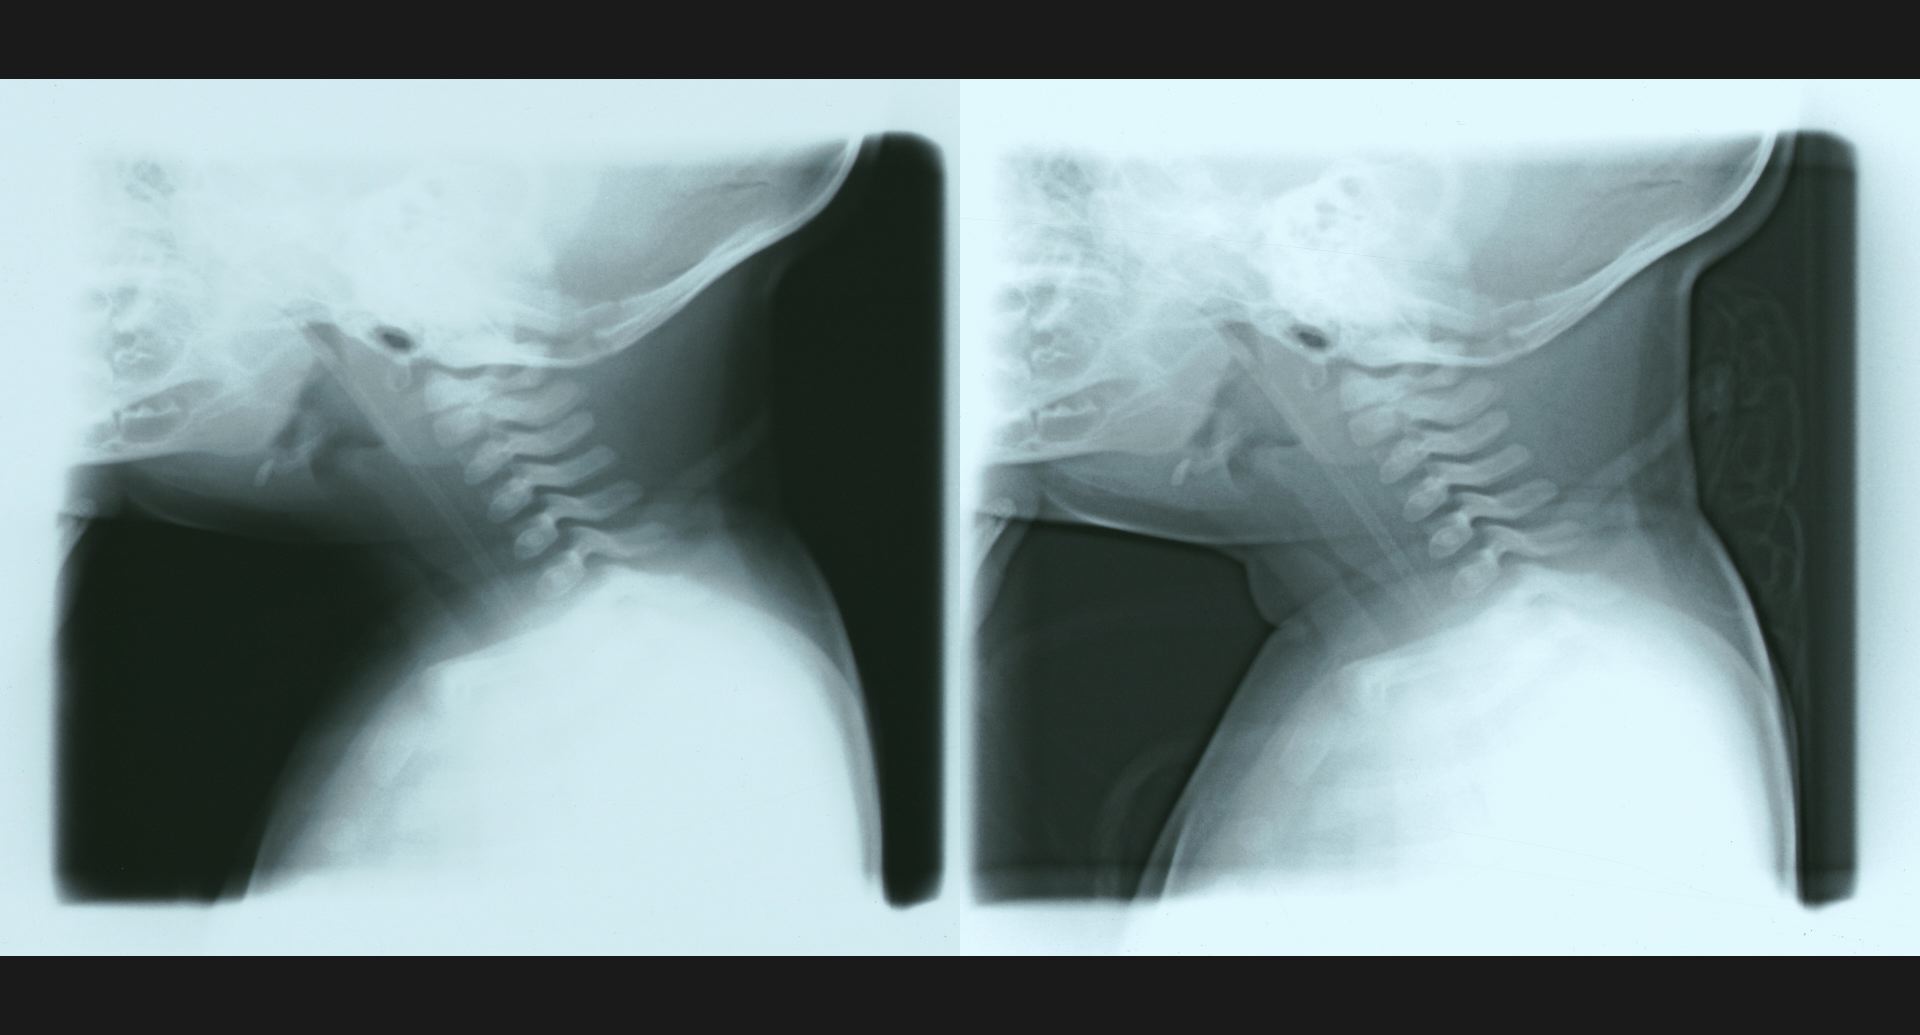

fig.3(105KB) :食道狭窄、肺炎

食道狭窄は、double aortic archによる。 肺炎は、造影の細かいところ。